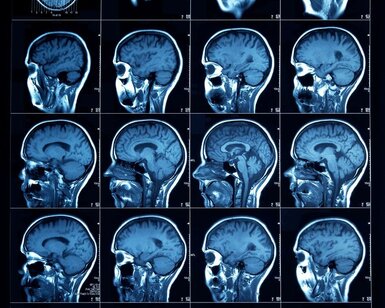

The project partners publicised the metrological developments for electronic brachytherapy and were able to contribute to several standards more